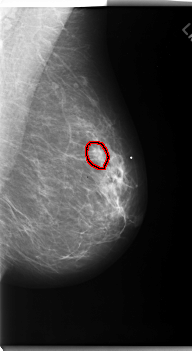

C_0170_1.LEFT_CC

FILE: C_0170_1.LEFT_CC.OVERLAY

TOTAL_ABNORMALITIES 1

ABNORMALITY 1

LESION_TYPE MASS SHAPE ARCHITECTURAL_DISTORTION MARGINS SPICULATED

ASSESSMENT 5

SUBTLETY 5

PATHOLOGY MALIGNANT

TOTAL_OUTLINES 1

BOUNDARY